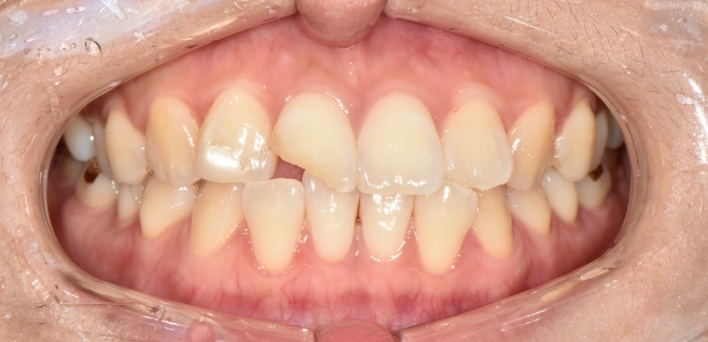

※ 더서울치과의원은 의료법을 준수하며 위 케이스는 실제 환자의 동의를 얻은 사례로 치료 전, 후가 동일한 환경에서 촬영되었습니다.

환자 케이스에 따라 부작용이 발생할 수 있습니다. 이 부분은 의료진의 충분한 상담과 체크를 통해 예방하고 줄일 수 있습니다.

[심미치료 부작용] 시술 후 치아 시림, 보철물 파손 등의 부작용이 발생할 수 있어 개인별 치아 상태에 따른 정확한 진단과 사후 관리가 중요합니다.

그저 예쁘기만한 부자연스러운 라미네이트가 아닙니다.

더서울치과의원은 각 개인의 얼굴 특성에 맞는 맞춤형 라미네이트를 선물합니다.